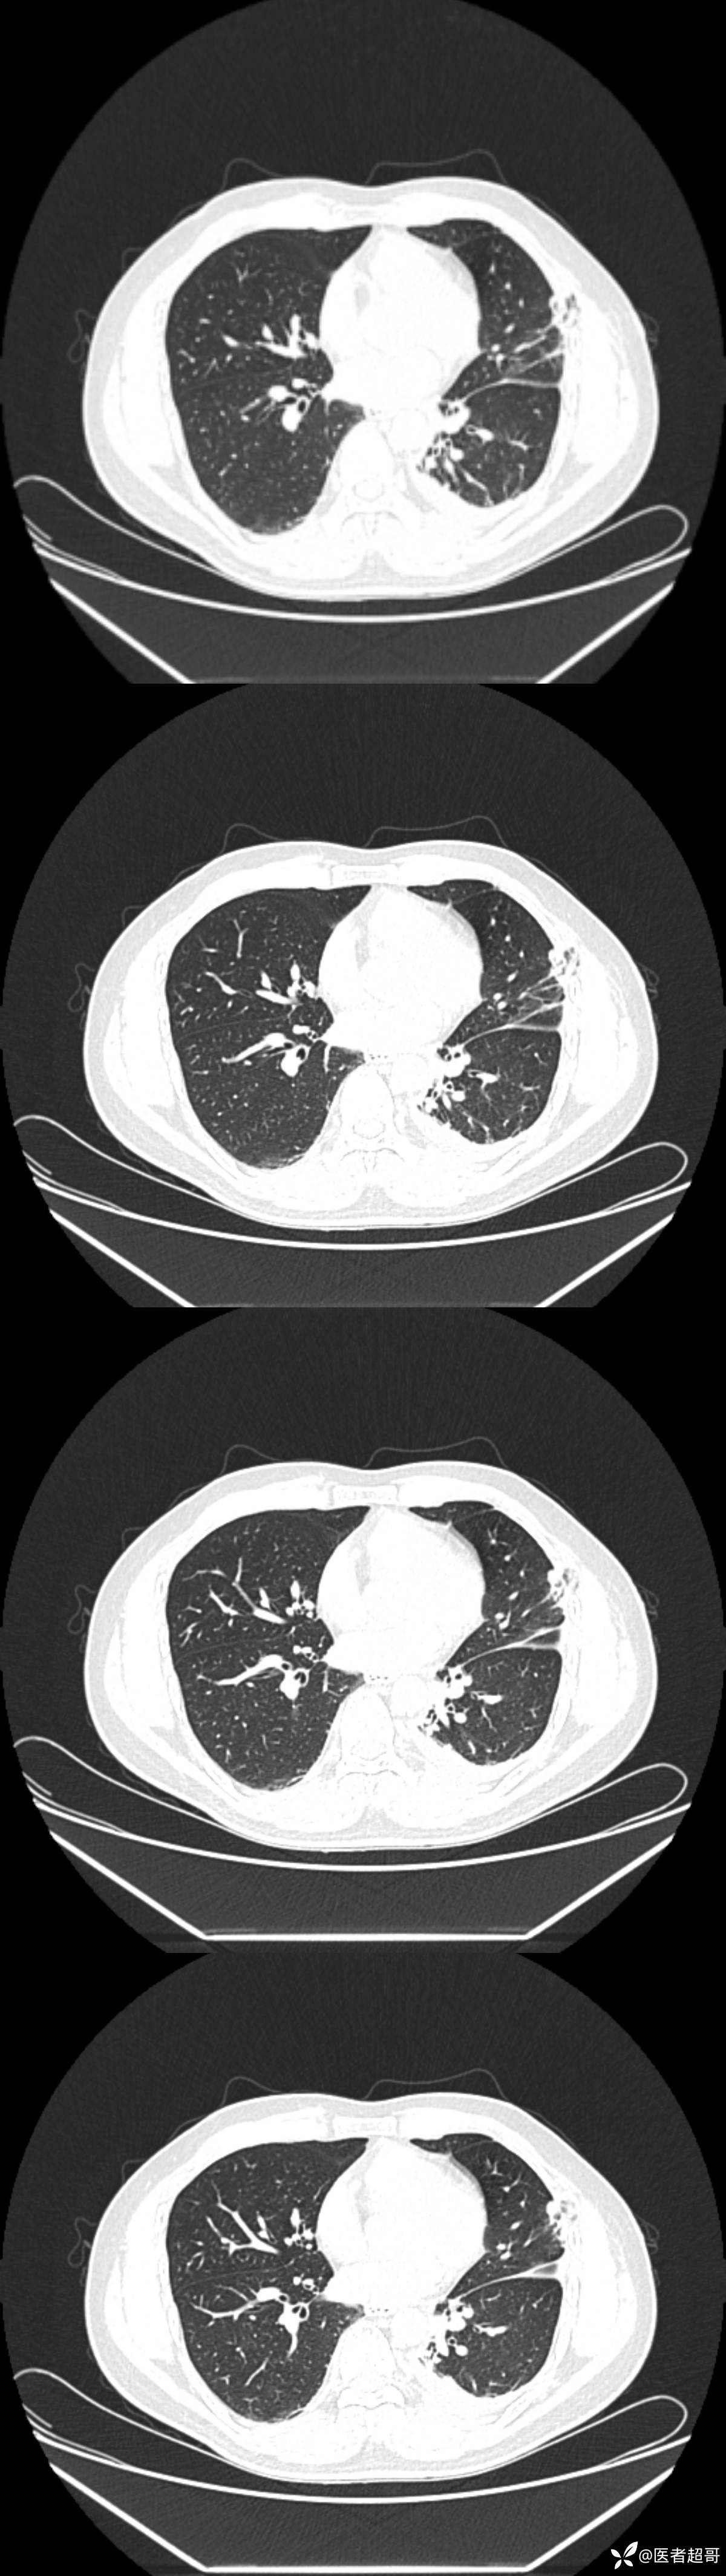

男38岁,胸痛

既往病史:患者自诉无明显诱因出现左侧胸部疼痛1天,无发热、咳嗽,无胸闷咳嗽,主诉:左侧胸部疼痛1天 体格检查:神清,胸廓无畸形,左侧胸壁轻触痛

流行性胸痛 (38)